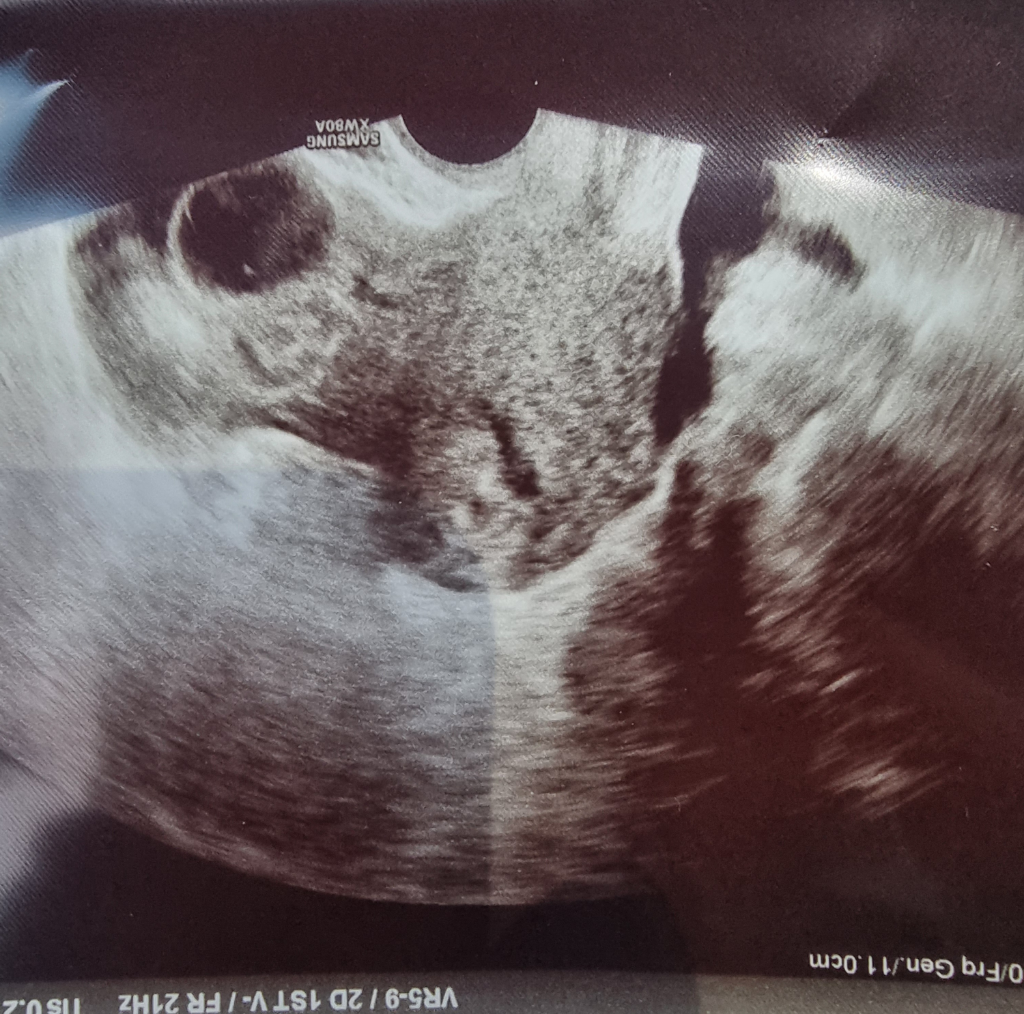

와이프가 임신이라는데 초음파 사진 중 어디가 아기집인가요?

와이프가 병원을 다녀오고 나서 사진을 보내줬는데.. 어디가 아기집인지 몰라서.. 알려주실 수 있을까요? 5주차 0일이라는데..

직접 본 초음파가 아니고 아기집이 명확히 잡힌 초음파 사진이 아니라 부정확할 수 있지만 참고하시면 되겠습니다. 다음 산부인과 진료 시 다시 아기집 확인하세요.